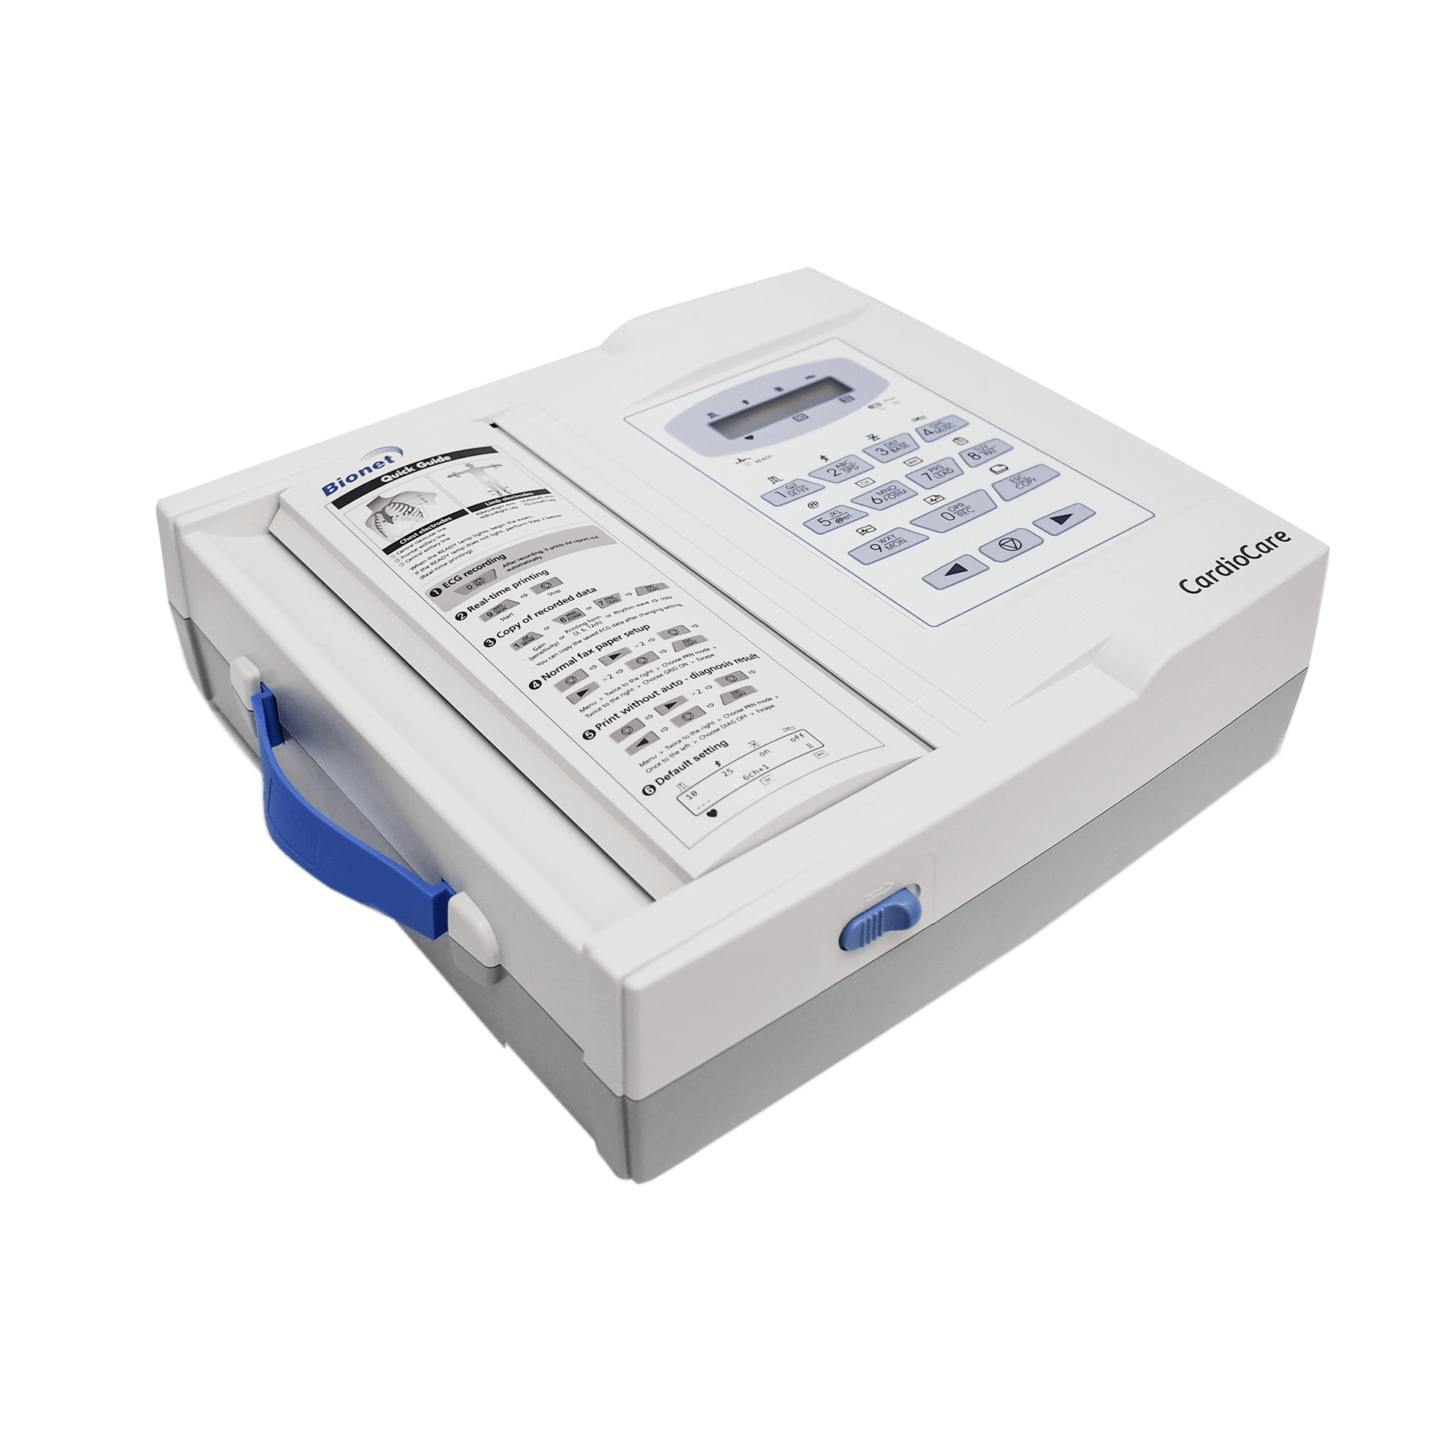

Bionet CardioTouch 3000 12 Channel ECG Machine

Bionet CardioTouch 3000 12 Channel ECG Machine

CardioCare 2000 ECG

CardioCare 2000 ECG